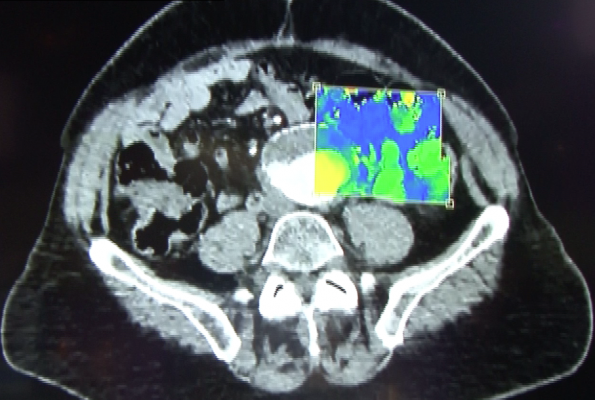

The emerging market trend is fusion of nuclear imaging with different diagnostic imaging products such as PET/CT, SPECT/CT, and MRI/PET (magnetic resonance imaging). This provides a full gamut of imaging scans through the same unit and at the same time. The PET market is expected to witness more growth compared to SPECT imaging, as it provides higher resolution images, and the lack of availability of technetium-99m is propelling the industry to look for alternative diagnostic procedures.

Analyzing the application segment of SPECT and PET, PET is majorly being used in oncology because of good quality of imaging. SPECT, however, is mostly being used in the cardiology segment, accounting for almost 90 percent of the market share in cardiology. North America has totaled 5,729 PET procedures, while the number of PET procedures in the Asia-Pacific region is 369,636, owing to the increased demand of nuclear medicine diagnostic procedures in developing nations.